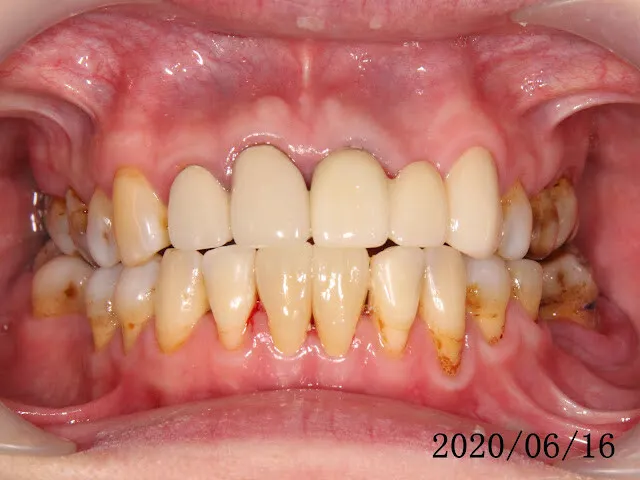

假牙材質2臨床案例...不同的假牙材質+牙齦萎縮